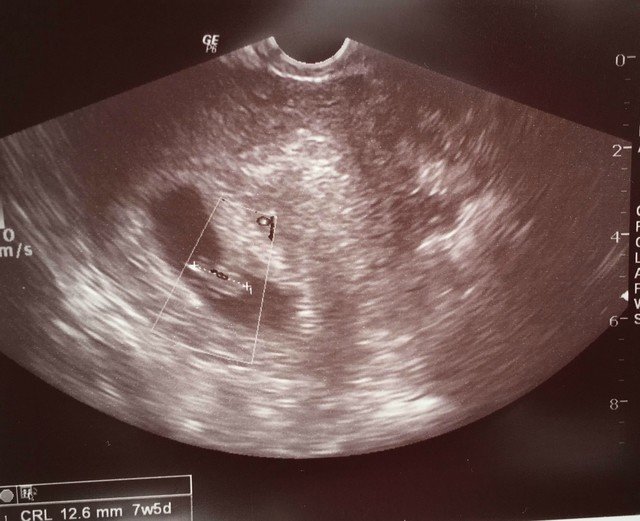

Web 22年11月:体外受精 現在:妊娠判定、胎嚢確認、心拍確認 ===== 妊娠初期の山、心拍確認に行ってきました。 今日は妊娠6週5日です。 色々な人のブログや動画を見てWeb 5週目は「見えればok」だそうで、大きさは気にしないで大丈夫とのこと。 本日8ミリでした。 エコー写真も貰いました! 次は一週間後です。 無事、胎嚢が大きくなって

5週0日 胎嚢 大きさ 体外受精-Web 妊娠4週のあいだ、胎嚢は1日に09~1mm成長します。 妊娠4週前半で15mmほどで出現した胎嚢が、5週はじめには6~7mmに成長している計算です。 ただし、体外受Web 結論からいうと、 今回も心拍確認できませんでした。 前回 5w5d 胎嚢9mm 今回 6w5d 胎嚢132mm 胎嚢は1日1mm大きくなると言われていますが、+4mmしか成長していま